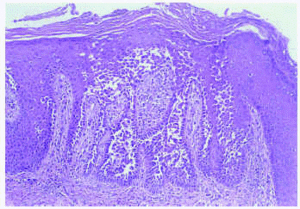

El hemograma y la bioquímica de rutina fueron normales. Se practicó una biopsia de una de las lesiones del cuello (figs. 3 y 4).

Fig. 3.--Biopsia cutánea de las lesiones.

Histopatológicamente, en la epidermis se observaban hendiduras suprabasales que contenían queratinocitos acantolíticos. Algunas de las células mostraban disqueratosis, pero no se apreciaban cuerpos redondos. La superficie de la epidermis se mostraba hiperqueratósica, con orto y paraqueratosis. En la dermis existía un moderado infiltrado inflamatorio perivascular compuesto por linfocitos e histiocitos.

El estudio histopatológico se caracteriza por la existencia de acantolisis, edema intercelular, aspecto de «pared en ladrillos desmoronada» de la epidermis y en ocasiones presencia de células disqueratósicas, hecho que plantea el diagnóstico diferencial con la enfermedad de Darier. El estudio con inmunofluorescencia directa e indirecta es negativo, a diferencia de las enfermedades ampollosas autoinmunes. Con el microscopio electrónico se observa un defecto en la adhesión desmosómica, con separación de los tonofilamentos9.